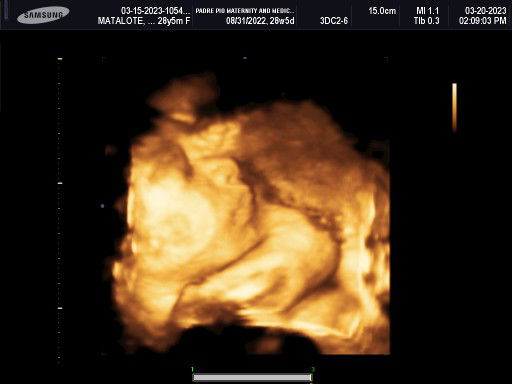

Mga mie, ask ko lng opinyon nyo if nasa sitwasyon ko kayo. Nagpa-ultrasound ako kahapon, sabi ni OB na nag uultrasound estimated wt ni baby is around 3.2-3.3 kls @37wks pero pagkita ko sa printed ultrasound result, 3.39kls na sya. Borderline for Large Gestational Age. Sa Friday ako babalik sa mismong OB ko, pero iniisip ko na baka magpacs nlng ako or ipilit ang normal? May budget naman kmi. Naisip ko lang na baka kpag pinilit ko normal, mahirapan ako mauwi din sa E-CS. Kapag CS naman, mas matagal healing time. Palagay nyo mga sis? Salamat ha! Pasensya na sa abala.

Mga sis, update ko lang. Di pumayag si OB na mag CS ako dahil wala daw indication for Cs unless nasa 4kgs si baby. Minsan daw kc malaki sa ultrasound pero maliit lang sa actual. Subukan daw muna namin magnormal, if 39wks at wala pa pagbibigyan nya akong mag CS. Niresetahan nya ako prim rose 2pcs ipapasok sa pwerta every night for 5days at meron din iinumin 3x/day for 3days. Balik ako Wednesday 🙏🏻